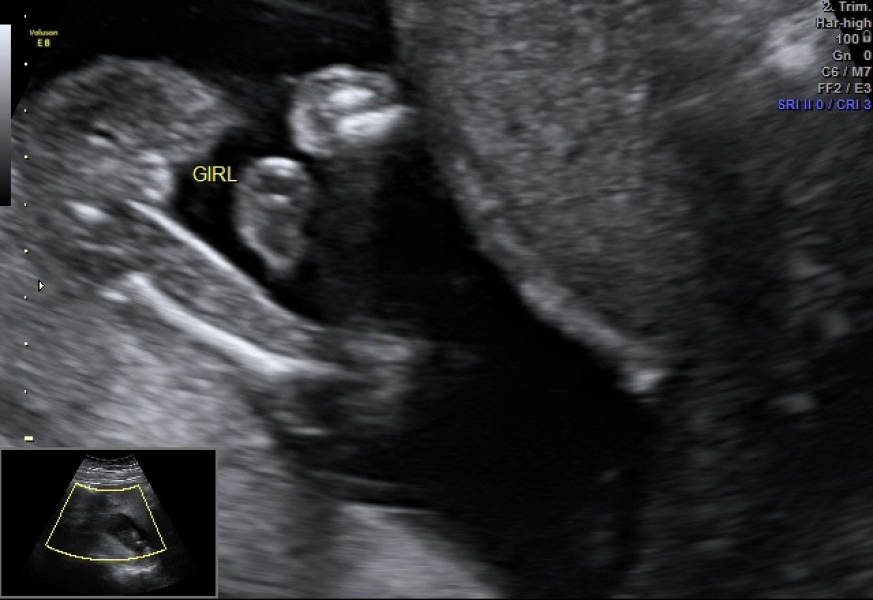

I’m a new mum stressing about the gender of our baby - it was our 16 weeks & 3 days scan would you say it’s defiantly a girl or would you say it’s wrong please help

It was a private scan with peekababy - previously deleted my other post due to wrong picture.

As a first time mum - and my family saying looks more like a boy - so getting me questioning sorry for asking the question.

Because my family saying looks more like a boy. We wanted find gender out for personal reasons.

with my last pregnancy we had a private scan at 16 weeks and were told the sex and it was correct, I don’t think there is anything to worry about.